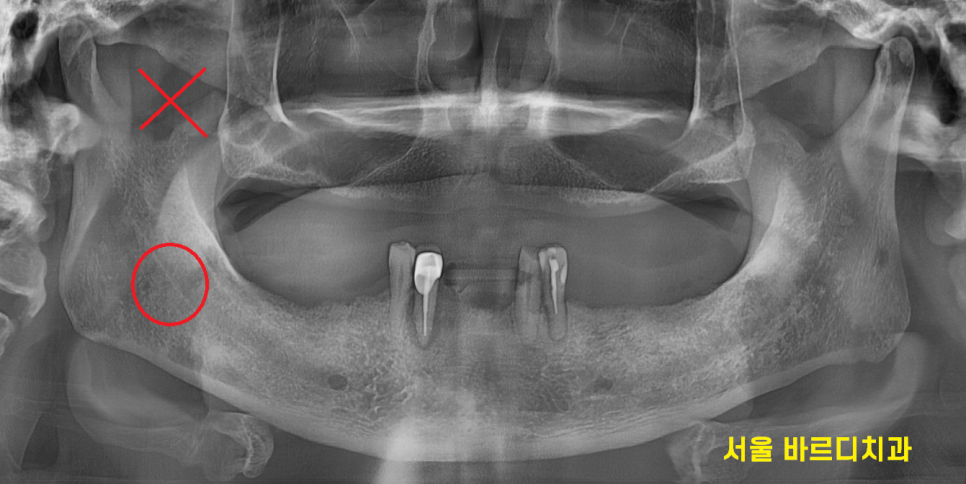

이런 경우에는 윗니는 치아가 1개도 없으니

보험 임플란트는 적용이 안될 것이고

아래 치아는 앞니 4개가 남아있으니

국가 지원 임플란트 혜택을 보실 수가 있겠습니다~